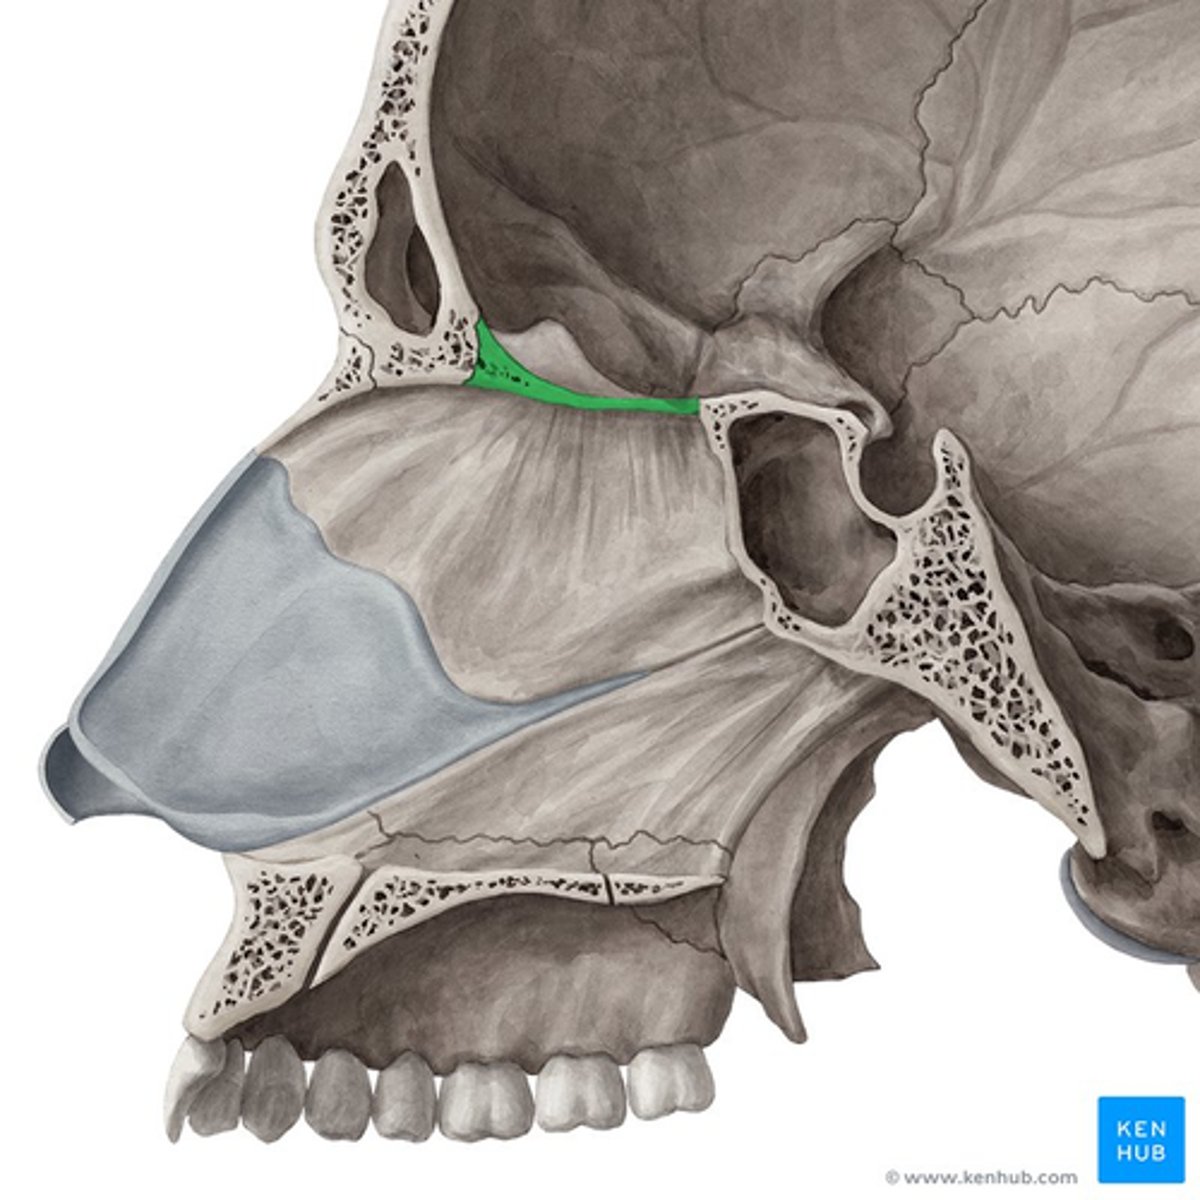

cribriform plate

anterior cranial fossa

frontal bone

nasal bone

ethmoid bone (perpendicular plate)

palatine bone (horizontal plate)

maxilla (palatine process)